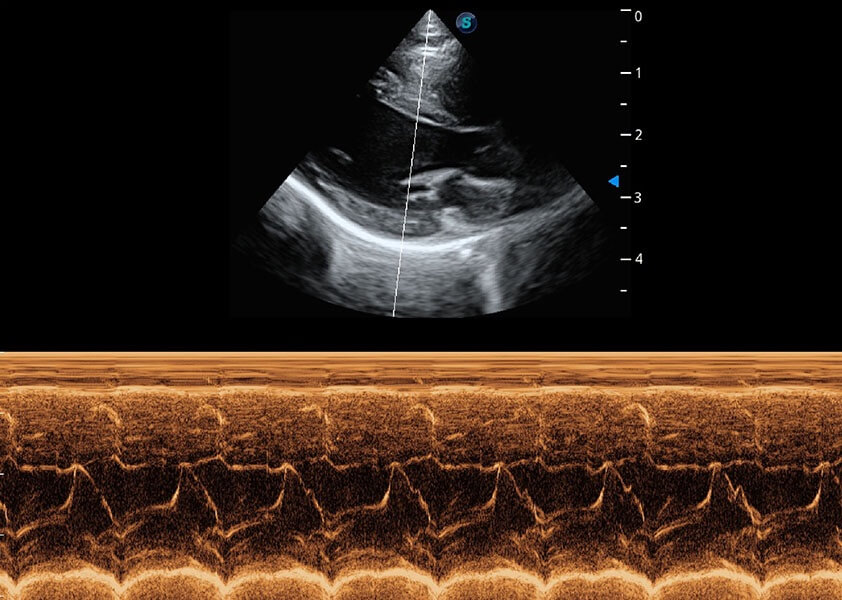

ProPet 60 作为一款高端台式动物超声设备,为动物医生的日常诊断提供了一系列贴合动物临床需求、解决临床实际问题的高级成像功能。凭借全系列高清探头,满足医生对腹部、心脏、生殖、浅表、肌骨等成像的所有需求,切实帮助您提升检查效率,提高诊断信心。

动物是人类最亲密的朋友和最值得信赖的伙伴。1xBET也一直致力于探索动物专用的超声影像解决方案。 全新推出的ProPet系列,是1xBET在动物超声影像智能化、专业化、精准化的一次跨越式革新。动物不能用言语来表述自己的不适,通过超声影像,ProPet系列搭建了动物医生与不同物种沟通的“桥梁”,为动物医生注入了“治愈之力”。